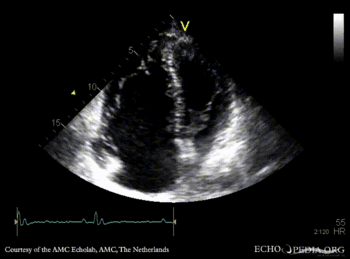

Ebstein anomaly

A4CH: high insertion of tricuspid valve A4CH: Color Doppler, severe tricuspid regurgitation